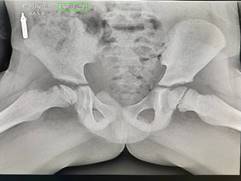

Se solicitó una radiografía de pelvis ósea en cuerpo de guardia en vista anteroposterior (Ver Fig.1) y en vista de rana (Ver Fig.2), donde se muestra una alteración del contorno superior de la cabeza femoral derecha, y se observó una imagen lineal que corresponde a una fractura subcondral. Además, se percibió el signo de la media luna de Waldestrom. Esto coincide con la etapa fragmentación, es clasificada así según los criterios de Herring en Grupo B, ya que existen cambios en la altura del pilar lateral (>50 %) y por ende el pronóstico es reservado.

Fig.1 Radiografía de cadera en vista anteroposterior.

El diagnóstico de este caso se basó en anamnesis detallada, examen físico (claudicación, dolor y limitación en rotación interna) y radiografías (vistas AP y rana); lo anterior reveló fractura subcondral y signo de Waldenström, signos inequívocos que clasifican el caso en grupo B de Salter-Thompson (>50 % afectación epifisaria), asociado a pronóstico reservado sin intervención temprana. (5)